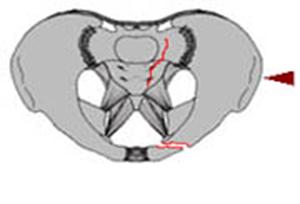

TRAUMATISMELE PELVIENE

Banda de stabilizare Dallas Fractura de bazin. Radiografie in

incidenta AP

Fractura de bazin

. Radiografie in incidenta AP Fractura de spina

Fisura de sacru si fractura ipsilaterala de ram pubian Fractura Straddle

Fractura Malgaigne Fractura Malgaigne. Imagine CT